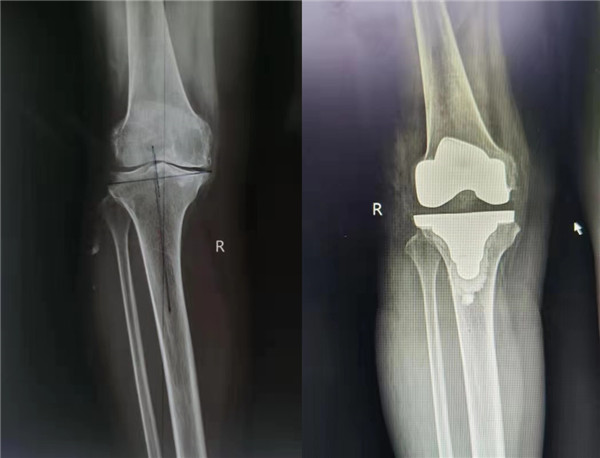

6月9日,由中华医学会骨科学分会候任主任委员、西安交通大学第二附属医院关节外科中心主任王坤正教授主刀,杨佩主任医师、王春生副主任医师、田润副研究员协助,成功完成了我国首例国产髋膝兼容关节手术机器人辅助全膝关节置换手术。

该手术使用的“ARTHROBOT”七轴髋膝兼容关节手术机器人,在术中可对膝关节活动度、下肢对线与关节间隙进行实时评估,依照术中实际情况实时调整规划方案,并按规划精准完成股骨与胫骨侧的截骨,误差控制在1mm与1˚范围以内,实现膝关节个性化、精准化手术治疗。